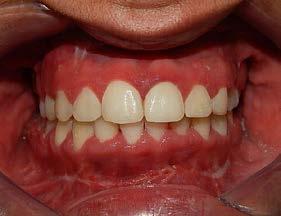

Figura 12. Panorámica de progreso. Figura 13. Frente, derecha e izquierda de progreso

En los estudios intraorales de progreso en la fotografía de frente se observa la mejoría el overjet y overbite (Figura 13), así como la coincidencia de las líneas medias dentarias. Se obtuvo las relaciones clases I caninas y molares para la obtención de la máxima intercuspidación, y para el paralelismo radicular se utilizaron arcos de acero, así como la oclusión funcional, con el detallado rectangular 0.019 × 0.025 superior e inferior, dobleces de primer, segundo y tercer orden y elásticos en W.

Se logró la corrección del overjet , overbite y la coincidencia (Figura 16) de las líneas medias dentarias, cierre del espacio anterosuperior.